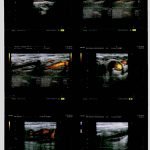

stenose-carotide-interne-droite